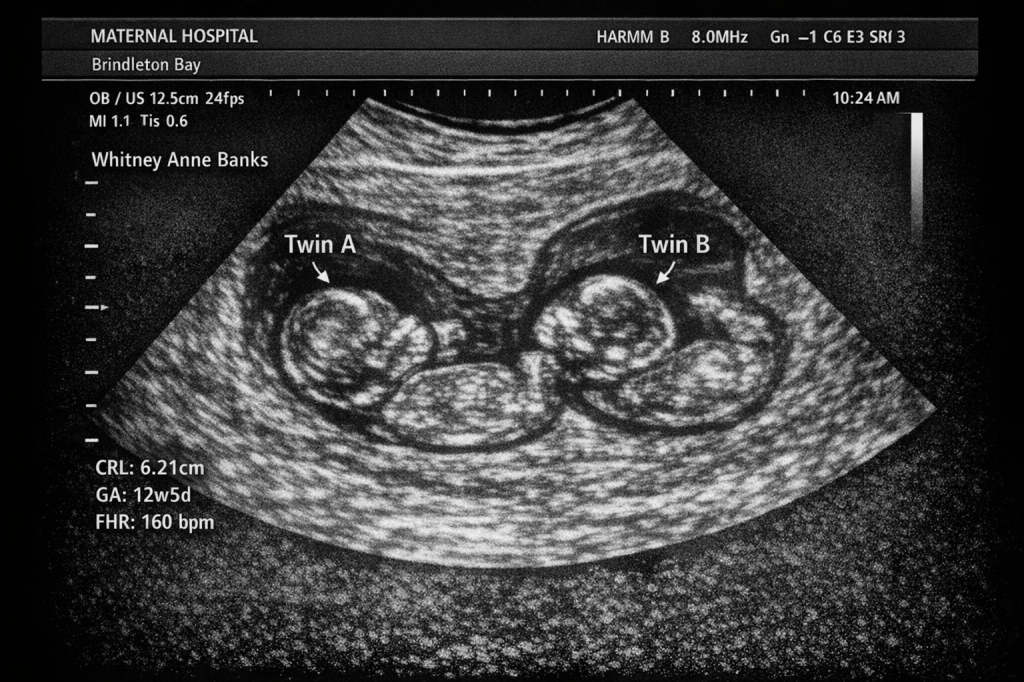

Whitney stepped forward just ahead of me. She dropped her handful of earth… then bent down and placed something gently on the casket. A photo.

“I will always love you,” she whispered. “And I will carry a part of you into forever.”

I lifted the shovel — heavy as grief — and looked down at the photo.

It wasn’t a snapshot.

It was a sonogram.

A strangled, involuntary sound tore out of me — something between a gasp and a sob, sharp enough to cut through the murmuring crowd. Within seconds Mom was at my side, Brad right behind her, Lauren clutching his arm. All three stared down at the sonogram with me, their faces collapsing in fresh, stunned grief as the truth settled over us like a second burial.

Brad leaned closer, blinking hard. His hand trembled as he reached out, picking up the image.

“Oh my God,” he whispered.

We all froze.

“Two,” he said again, voice cracking. “Twins. GA 12 weeks and 5 days? Almost 13 weeks along …”

And then, for the first time in his entire medical career — Brad Cunningham, trauma surgeon, Owner and Chairman of the Board of a world-wide medical empire, the man who had held lives in his hands more time than any of us could count — simply fainted at his late son’s grave, as the sonogram slipped from his grasp and drifted like a feather down into the grave, landing softly atop Graham’s coffin.